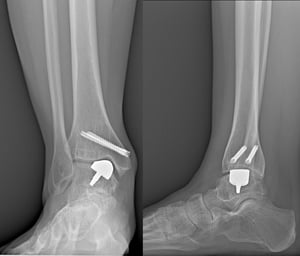

Nell’immagine si possono notare i componenti della protesi di caviglia mobile bearing (dall’alto verso il basso):

- Protesi di caviglia Hintegra® “mobile bearing” completa;

- Protesi di caviglia Hintegra® “mobile bearing” – componente talare;

- Protesi di caviglia Hintegra® “mobile bearing” – componente tibiale;

- Protesi di caviglia Hintegra® “mobile bearing” – inserto